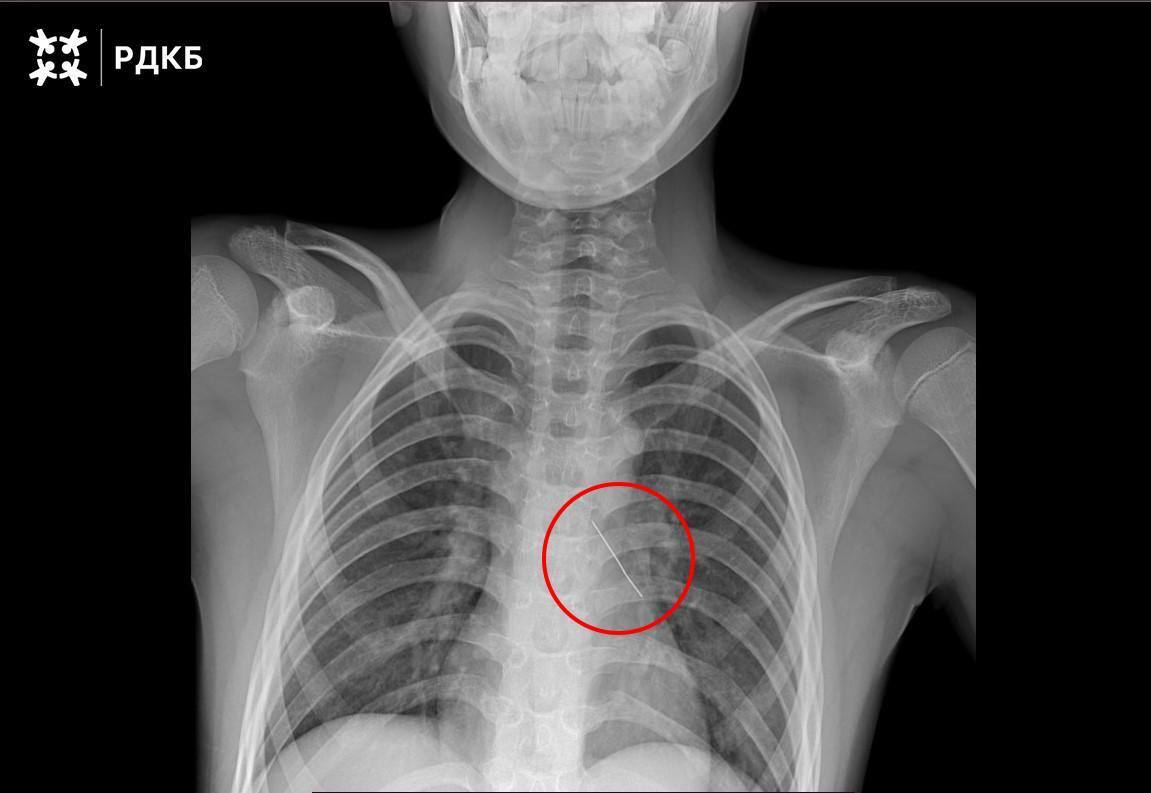

При поступлении мальчик мог говорить только шёпотом и жаловался на сильные боли в груди. Рентген показал, что булавка находится в области нижней доли левого бронха. Об операции рассказал заведующий отделением реконструктивной и восстановительной хирургии грудной полости РДКБ Евгений Андреев:

«В ходе малоинвазивного вмешательства мы завели эндоскоп в левый главный бронх ребёнка, а при осмотре его нижней доли обнаружили скопление мокроты. После её удаления визуализировали предмет округлой формы — колпачок французской булавки. Инородное тело было изогнуто и острым концом пронзило бронх пациента.

Булавку аккуратно извлекли под визуальным контролем с помощью оптических щипцов, это позволило минимизировать кровотечение. Контрольная рентгенография показала, что свободного воздуха в грудной полости нет.